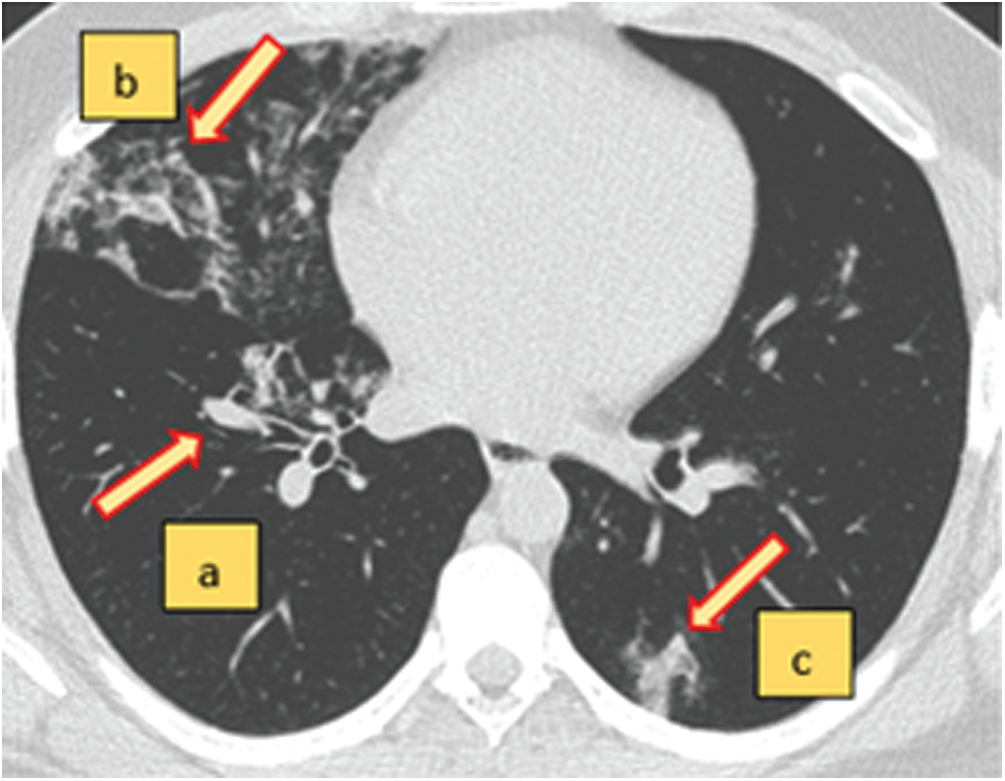

The SARS-CoV-2 CT-scan dataset [27] was used to evaluate the proposed COVID-19 detection system. Fig. 7 shows the interpretation of a sample chest CT scan with COVID-19 positive features indicated by arrows. A total of 1688 COVID-19 chest CT scans were used for evaluation. Fig. 8 shows sample CT scans from the dataset. The samples were split into 65% for the training set, 20% for the validation set, and 15% for the test set. To determine the model performance, it should be tested on unseen data. Therefore, the dataset was split for training, validation, and testing. To further improve the diversity of the CT scans for training, we used data augmentation by applying operations of rotation, shifting, and flipping (Fig. 9). The validation and test sets are not augmented to determine the detection error on real data.

Figure 7: An axial view of a chest CT-scan image with characteristics of COVID-19 (+ve) disease (a–c). The red arrows indicate the regions of abnormal manifestations. (a) Onset of lung lesion formation near the centre. (b) Peripherally distributed consolidation with GGO. (c) Shadow of ground glass opacities (GGO) in the lower right region of the CT-scan